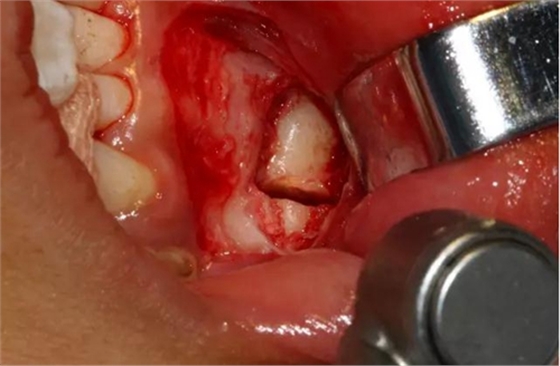

設計冠切的位置

橫斷牙冠,注意深度的把控

為了減少骨創(chuàng),“T”型分割牙冠

去除冠部

本案例要點:1、患兒年齡小、手術的耐受性值得關注;2、阻生位置較深,麻醉的有效性很關鍵;3、埋伏阻生的位置處于下頜骨骨質好發(fā)部位--正中聯(lián)合,所以,術中不能采用任何錘擊劈冠的力量;4、由于采用渦輪機的微動力系統(tǒng),嚴防皮下氣腫的發(fā)生;5、術后加壓,防治水腫。